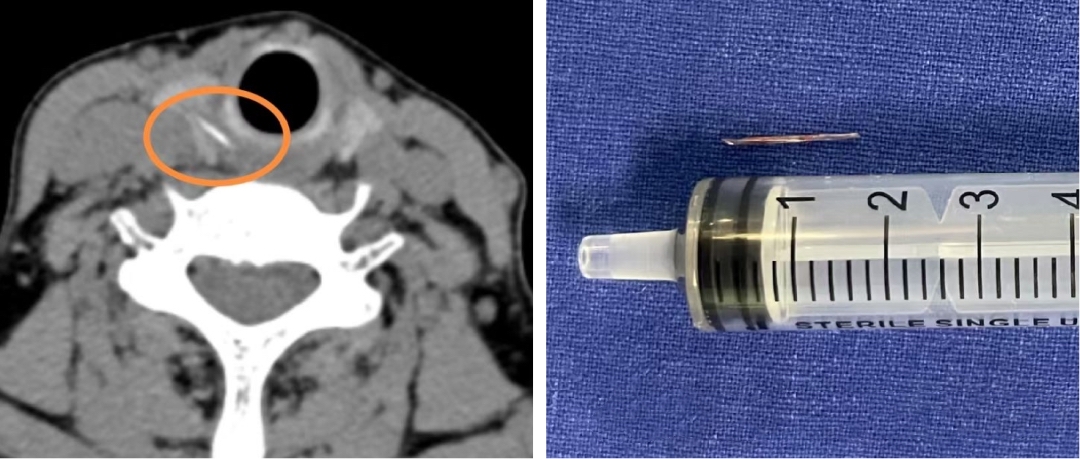

鱼刺究竟去了哪里?胃镜报告上的一句话“食管右侧入口处黏膜损伤”引起了医生的注意:鱼刺会不会已经从这里穿出去了?”颈部CT看来免不了了。果然,CT检查结果证实了之前的猜测:在右侧甲状腺位置,发现了一条索状的高密度异物影!极有可能是鱼刺穿透食管壁,扎进了甲状腺!

情况变得十分棘手。通过内镜微创手术,已无法取出这根“逃逸”的鱼刺。经过审慎评估,医生决定实施‌全麻下颈侧切开术,‌取出了一枚长约1.5厘米的鱼刺。探查还发现,周围的食道黏膜有轻度肿胀,便对创面作了仔细消毒。术后,L阿姨喉咙的疼痛明显减轻,经过抗炎治疗,颈部的切口愈合良好。